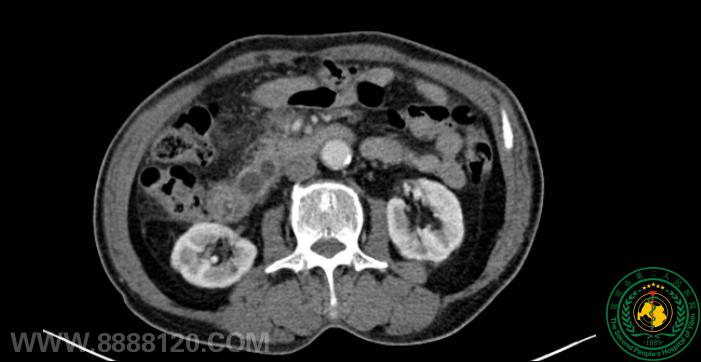

宜宾市第二人民医院 图文